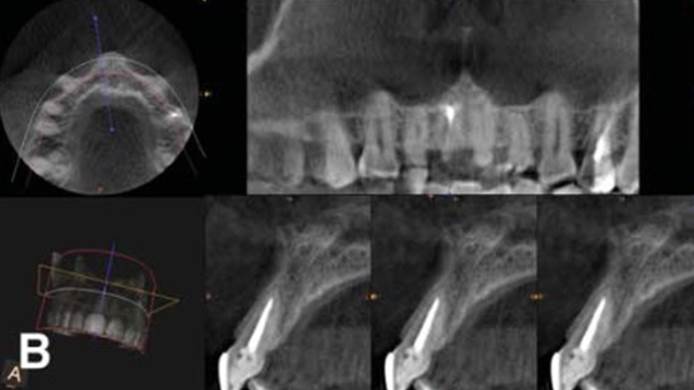

Clinical case: Bone filling into the bottom of deepest thread at 8.0mm AnyRidge fixture

- Courtesy of Dr. Kwang Bum Park -

Keywords

AnyRidge, Knifethread ,extraction socket, ,initial stability ,Allograft, ,osseointegratio ,Dr. Kwang Bum Park, , Mandibular, Single replacement, AnyRidge, Mega-oss,

Products used

Implant system-AnyRidge, Regeneration-Mega-Oss